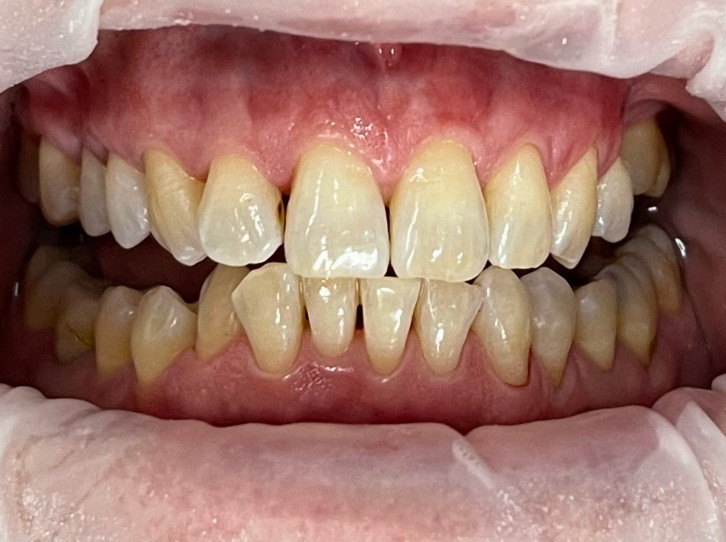

Initial Situation

The patient presented with heavy supra- and subgingival calculus. She had local areas of recession up to 3mm with PD up to 5mm. She is currently brushing once a day with no interdental cleaning.

Oral hygiene instruction was provided. The lower arch was conducted first, with the upper arch a week later due to the heavy presence of calculus. An OptraGate was used for both visits. Supra- and subgingival calculus was removed, followed by MyLunos® powder jet handpiece and Lunos® Prophy Powder Gentle Clean Spearmint. The patient was offered LA, but declined.

“I am amazed at the colour difference… I didn’t feel the need to be numbed up.”